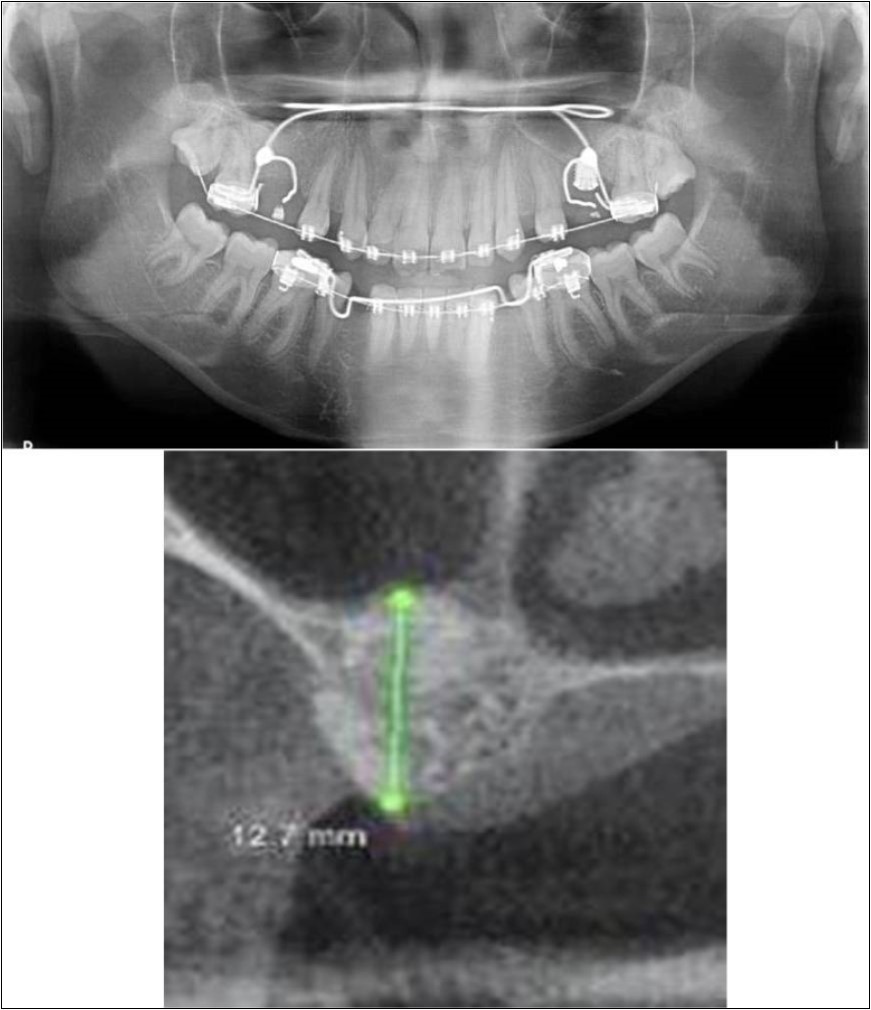

Treatment:

Patient underwent the procedure of indirect sinus elevation using sinus osteotomes in relation to 26 region. Calcium phosphosilicate putty was dispensed as the graft material through the crestal osteotomy site to maintain the elevated sinus membrane followed by placement of 5 x 10mm dental implant under local anaesthesia and strict aseptic protocols. The implant was allowed to osseo-integrate for a period of six months during which the patient was followed-up periodically and was assessed for peri-implantitis, crestal bone loss and mobility. Patient was taken-up for direct sinus elevation via lateral window approach for sinus augmentation i.r.t 16 region. Under aseptic conditions and local anaesthesia, lateral wall of maxilla was exposed after muco-periosteal flap elevation. A window was created of 1cm diameter corresponding to apical aspect of 16. Sinus membrane was identified and elevated using sinus elevators and reamers without perforating the lining. Once the sinus membrane was elevated, phosphosilicate putty was dispensed through the lateral osteotomy site as the graft material to achieve an augmentation of 1cm assessed clinically and confirmed using post-operative OPG. At the end of 6 months, a repeat CBCT scan was advised to evaluate the increase in bone height. (Figure 13a,b, pre-treatment; Figure 14a,b, post-treatment)

Figure 13.(a,b) Pre-treatment OPG and cross section of CBCT showing residual alveolar bone height for Case No.4;

Figure 14.(a,b) Post-treatment OPG and cross section of CBCT showing residual alveolar bone height for Case No.4;